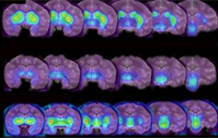

Le CEA-I2BM, en partenariat avec Orphachem et l'Université de Tours, a développé un procédé ultrarapide de marquage au fluor-18 de ce radio-traceur. Celui-ci est couvert par le dépôt d'un brevet européen et vient d'être transféré à la société Cyclopharma, dans le cadre d'un accord de licence exclusive, dans le but de développer un radiopharmaceutique pour le diagnostic différentiel de la maladie de Parkinson avec la TEP[1]. Le fluor-18 est un émetteur de positons à vie brève de période radioactive 110 minutes. La radio-traceur marqué au fluor-18, le [18F]LBT-999, permet de visualiser et de quantifier grâce à la TEP le transporteur de la dopamine.

Illustration du principe de fonctionnement de la tomographie par émission de positons. © CEA/ Corinne Beurtey © CEA/ Corinne Beurtey